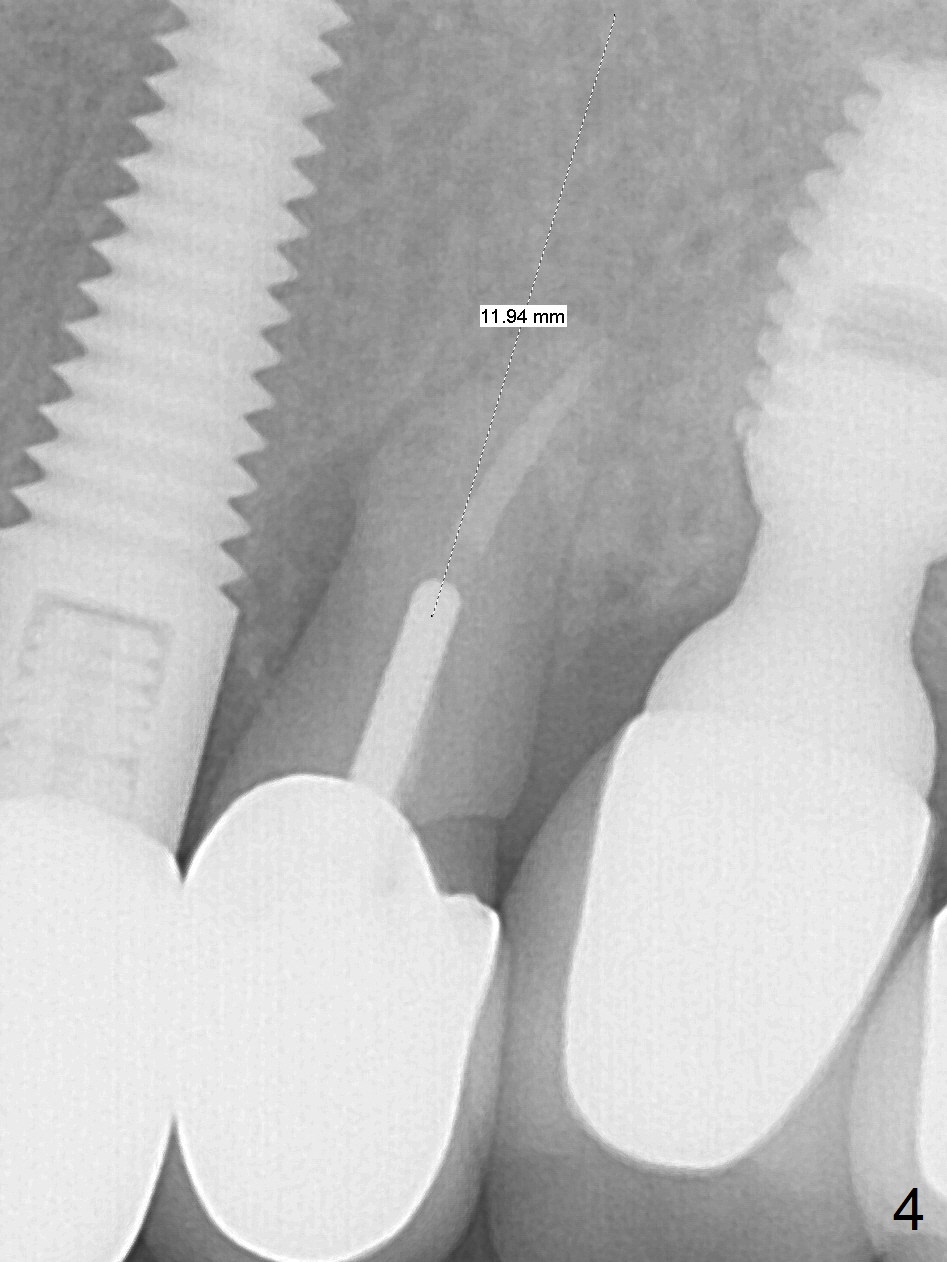

A 59-year-old woman has mild discomfort in the upper left quadrant, which is alleviated by salt water rinse. The buccal gingiva recedes at #13 with mesiobuccal swelling and deep pocket (Fig.1,3), corresponding to the mesial radiolucency (Fig.2 *). The tooth appears to have vertical fractured root, as related to the retention post. Since the root tip curves distal, the initial osteotomy (Fig.5 red) should be established in the mesioapical slope after extraction (black). Following initial entrance, the trajectory will be changed to the long axis of the space (Fig.6) with PA to be taken. Measure the depth of the buccal crest against the buccal, proximal and palatal gingival margins. Place an implant, the same as #12 (4.5x20 mm) unless the mesiobuccal defect is extremely large (UF).